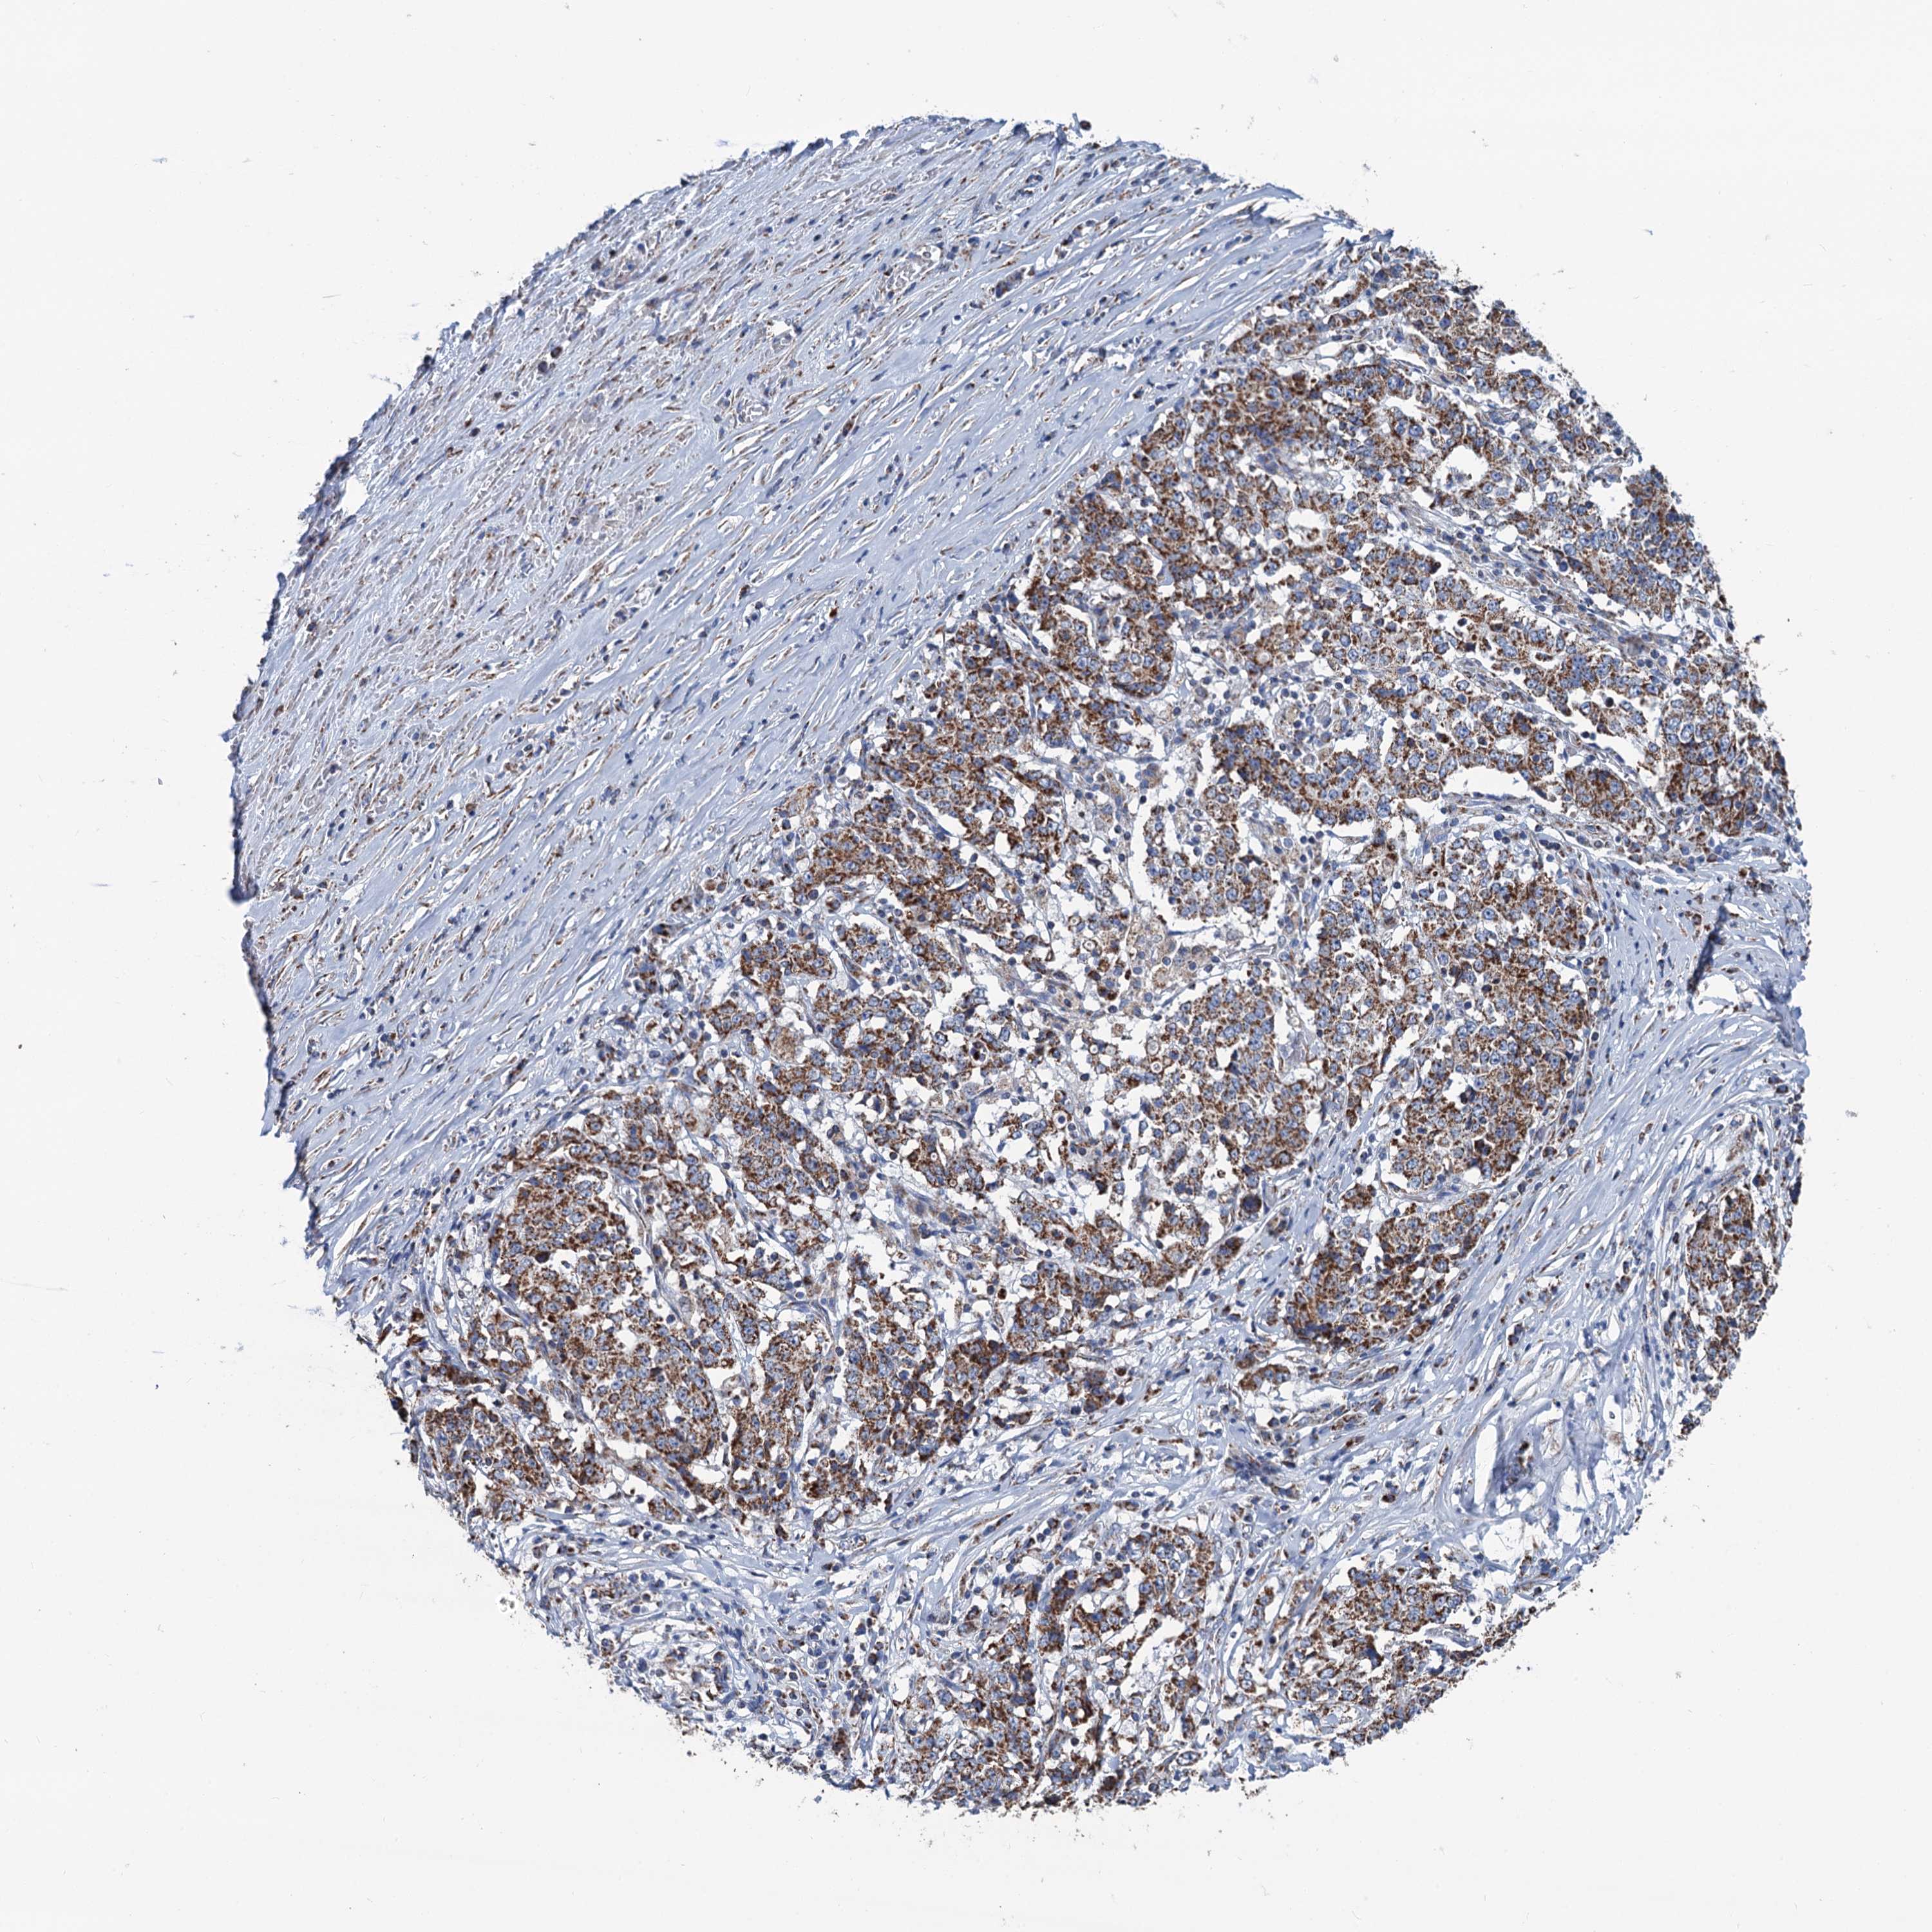

STOMACH CANCER - Protein expressioni

A mouse-over function shows sample information and annotation data. Click on an image to view it in a full screen mode. Samples can be filtered based on level of antibody staining by selecting one or several of the following categories: high, medium, low and not detected. The assay and annotation is described here.

Note that samples used for immunohistochemistry by the Human Protein Atlas do not correspond to samples in the TCGA dataset.

Antibody stainingi

Antibody staining in the annotated cell types in the current human tissue is reported as not detected, low, medium, or high, based on conventional immunohistochemistry profiling in selected tissues. This score is based on the combination of the staining intensity and fraction of stained cells.

Each image is clickable and will lead to virtual microscopy that enables deeper exploration of all samples and also displays staining intensity scores, fraction scores and subcellular localization as well as patient and tissue information for each sample.

Antibody HPA041391

Antibody HPA044250

Staining

High

Medium

Low

Not detected

Intensity

Strong

Moderate

Weak

Negative

Quantity

>75%

75%-25%

<25%

None

Location

Nuclear

Cytoplasmic/membranous

Cytoplasmic/membranous,nuclear

Adenocarcinoma, NOS

Adenocarcinoma, High grade